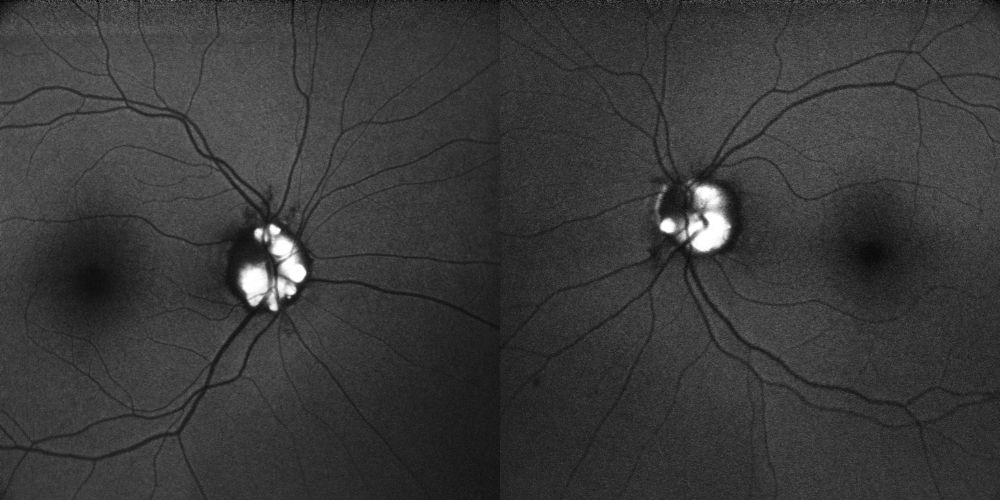

Retro-mode

Il retro-mode documenta in maniera particolarmente dimostrativa la presenza di multipli noduli iperluminescenti, clustered, multilobulati, distribuiti sulla superficie del nervo ottico e in sede marginale, con evidente effetto di pseudo-rilievo/pseudo-3D. Una delle due immagini risulta particolarmente esplicativa per nitidezza e contrasto, mostrando il carattere multinodulare superficiale del caso in modo molto intuitivo. Il pattern complessivo è altamente suggestivo di visible optic disc drusen.

Figura 4. Retro-mode. A sinistra, immagine con marcato effetto pseudo-3D della testa del nervo ottico e presenza di multipli noduli iperluminescenti clustered e multilobulati sulla superficie papillare e al margine. A destra, immagine particolarmente dimostrativa per contrasto e nitidezza, con evidenza di numerose prominenze superficiali iperluminescenti compatibili con drusen papillari visibili. La lateralità delle due immagini retro-mode va confermata sull’export originale.